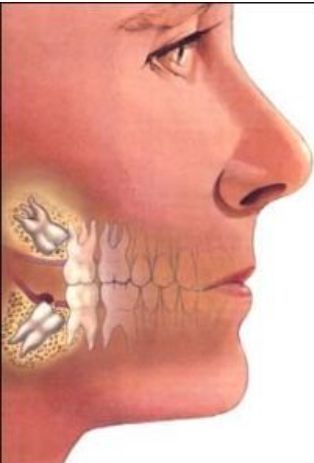

首先先给各位复习一下,什么是智齿:智齿是指人类口腔内,牙槽骨上最里面的上下左右各一的四颗第三磨牙。

因为这四颗第三磨牙正好在20岁左右时开始萌出,此时人的生理、心理发育接近成熟,于是被看做是“智慧到来”的象征,故称它为“智齿”,是口腔最靠近喉咙的牙齿。

智齿的位置从门牙牙缝开始,由一侧门牙向里数牙齿数目,如果有第八颗牙,它就是智齿。

从现代医学的观点看,智齿是人类进化的必然。智齿通常是在人类心智已经趋于成熟时才长出,因而得名。

智齿向前生长挤压到邻牙。此外,向后、向舌侧、向颊侧、甚至向下长也都可能产生危害。

智齿生长方向不正常,通常会导致智齿与相邻的磨牙间出现缝隙或凹槽,极易嵌顿食物残渣,长时间清理不净,相邻磨牙将发生龋齿、牙髓炎、根尖炎等。